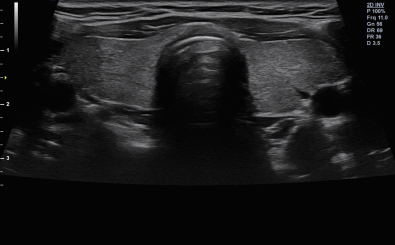

CLINICAL IMAGES

臨床影像

Thyroid